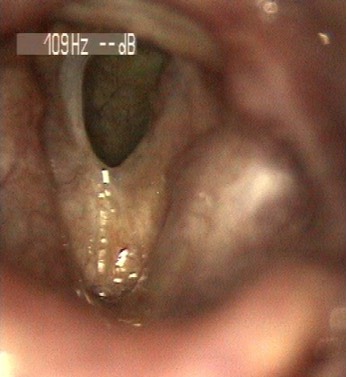

2681. Данная ларингеальная картина характеризует